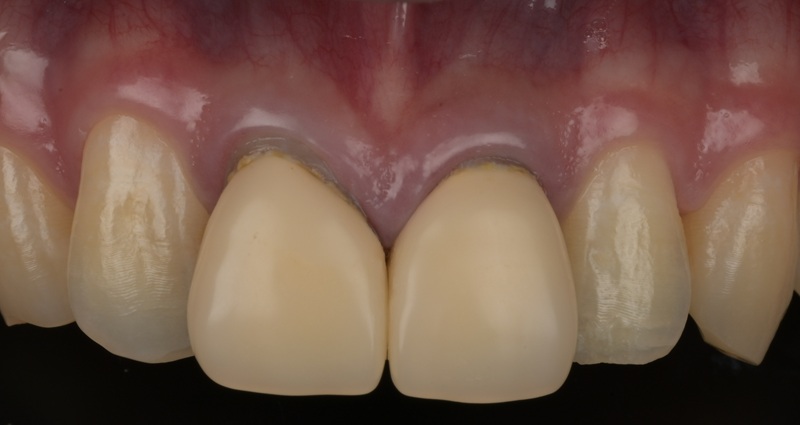

術前

以前に治療された前歯の被せ物の見た目を気にされ、再治療をご希望されました。 審美性だけでなく、内部の根管治療まで丁寧に行うことで、将来的なトラブルのリスクを抑えた、長期的に安定した治療結果を目指しました。 |